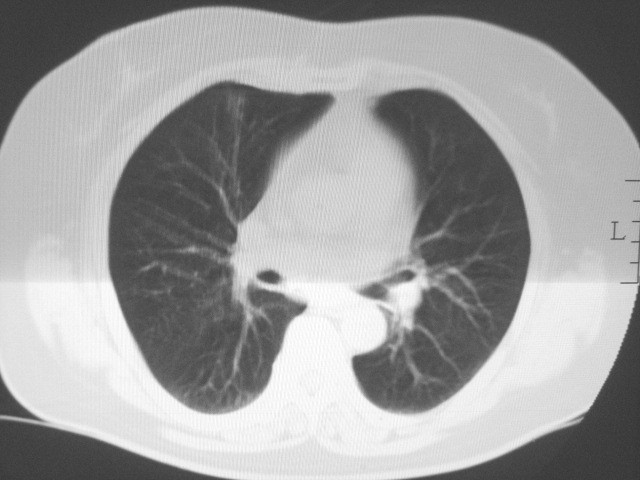

以下是引用清清楚楚在2007-8-28 7:13:00的发言:[br]右肺下叶可见斑片状高密度影,边缘模糊;右肺中叶内侧段及左肺舌段亦可见小斑片状模糊影。[br]考虑双肺感染,建议抗炎治疗后复查。

以下是引用天南地北在2007-8-27 23:49:00的发言:[br]右肺下叶可见斑片状高密度影,边缘模糊;右肺中叶内侧段及左肺舌段亦可见小斑片状模糊影。[br]考虑双肺感染,建议积极抗炎治疗后复查。

以下是引用天南地北在2007-8-27 23:49:00的发言:[br]右肺下叶可见斑片状高密度影,边缘模糊;右肺中叶内侧段及左肺舌段亦可见小斑片状模糊影。[br]考虑双肺感染,建议抗炎治疗后复查。

以下是引用难听在2007-8-28 13:17:00的发言:[br]右肺下叶背段支气管狭窄,是否可以考虑新生物伴阻塞性肺炎.请大家帮帮忙,这个病人是卫生局长的丈母娘.惹不起啊.